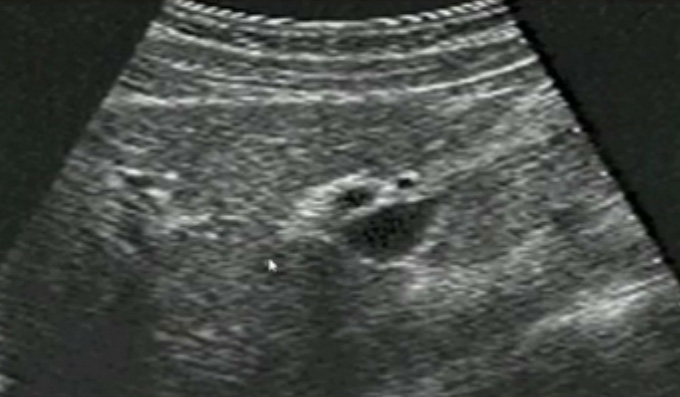

一、正常膽囊超聲圖像有的時(shí)候經(jīng)常發(fā)現(xiàn)檢查不到膽囊,其實(shí)有幾種可能性,檢查人員的技術(shù)不過關(guān)沒發(fā)現(xiàn)膽囊,就要找上級(jí)醫(yī)生會(huì)診,如果還是沒找到的話就不是技術(shù)問題。結(jié)石或腫瘤充滿膽囊,使其液腔消失,慢性膽囊炎使得膽囊萎縮或膽囊壁肥厚而囊腔消失患者已進(jìn)食,膽囊處于膽汁排空的狀態(tài),膽囊先天性過小或缺失;膽囊位置極端異常(可能很低或位于左側(cè))膽囊切除術(shù)后(注意詢問病史)。